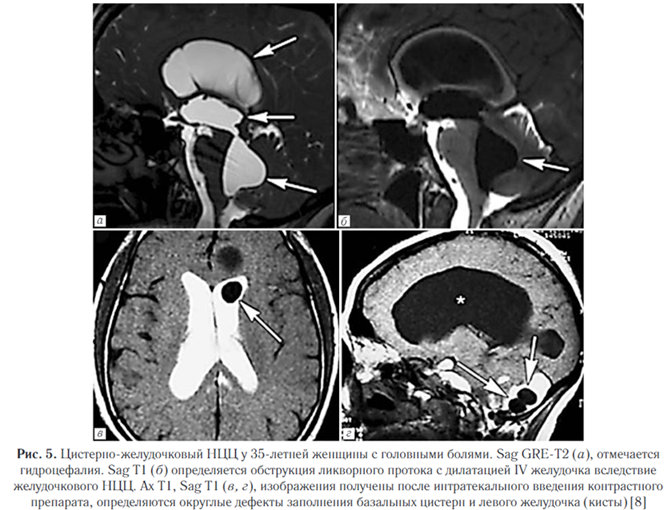

2. Везикулярная стадия (активная). Визуализи - руется полностью выросшая киста или скопление кист (по типу «грозди винограда») в базальных ганглиях, мозжечке, стволе мозга, цистернах или желудочковой системе, в паренхиме полушарий и в субарахноидальных пространствах. Сколекс встречается почти в 50% случаев. НЦЦ по типу «грозди винограда» наблюдается обычно вокруг рострального ствола мозга или сильвиевой щели, обычно лишен сколекса. Отек практически отсутствует (рис. 1).

Субарахноидально-цистернальный НЦЦ поражает субарахноидальные пространства и прилегающие мозговые оболочки, которые представляют собой наиболее распространенную локализацию паразитов (рис. 4).

Кисты также могут вызывать отек прилегающего вещества мозга с глиозом и васкулитом [8]. Внутрижелудочковый нейроцистицеркоз. Составляет от 0,7% до 33% всех случаев НЦЦ, часто сочетается с субарахноидальным.

Наиболее часто изменения выявляются в IV желудочке (50%), в боковых желудочках (35%), реже в III желудочке (10%) и в водопроводе (5%). При этом изолированный желудочковый НЦЦ (т.е. без вовлечения субарахноидального пространства) отмечается в трети случаев. Свободно плавающие в желудочках цисты вызывают синдром Brunsa, это состояние характеризуется интермиттирующей обструкцией желудочкового отверстия, приводящей к периодическим головным болям, головокружениям, преходящей атаксии и редко к синкопальным состояниям; интермиттирующая обструкция IV желудочка кистами с формированием арахноидита может имитировать феохромоцитому. Интравентрикулярные кисты вызывают гранулярный эпидидимит, который может сочетаться с гидроцефалией и прогрессирующей дисфункцией среднего мозга (рис. 5) [8].